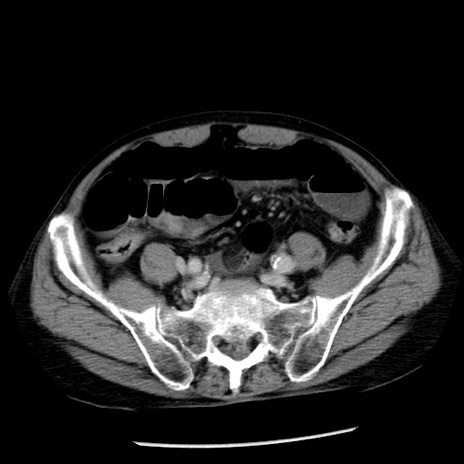

症例26(横断像)

冠状断像

【症例】80歳代男性

【主訴】嘔吐

【現病歴】昨晩2回嘔吐あり、今朝になっても嘔吐あり。来院。

【既往歴】胃潰瘍

【身体所見】意識清明、BT 37.6℃、BP 166/95mmHg、HR 100bpm、SpO2 97%、腹部:平坦・軟、腸蠕動音聴取良好、圧痛なし。

【データ】WBC 21900、CRP 1.46